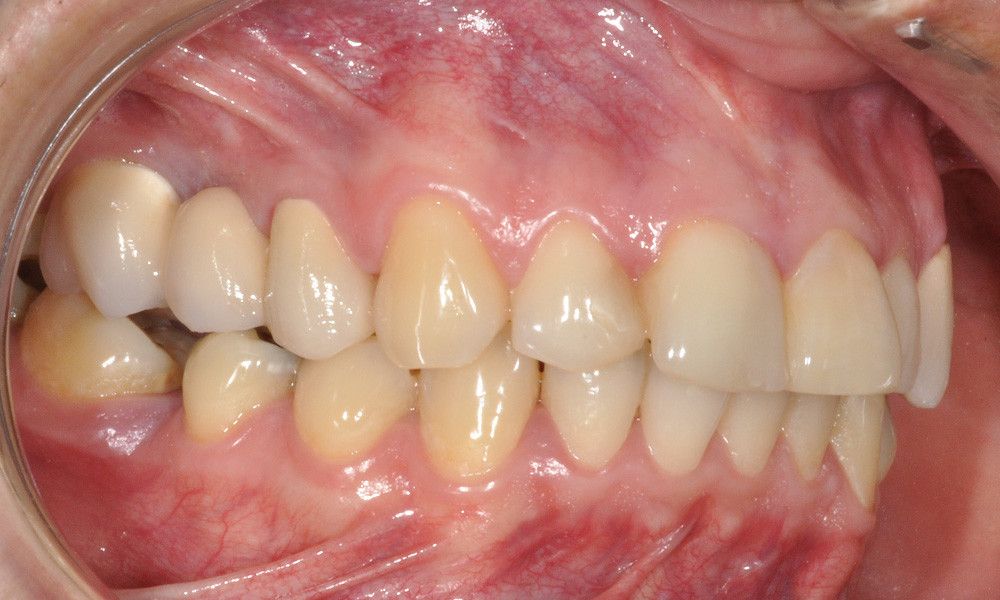

Reporte del Caso: Paciente sexo masculino, 36 años, con diagnóstico de esquizofrenia y trastorno bipolar en tratamiento. Consulta por el recambio de dos prótesis fijas plurales (PFP) de reemplazo de dientes 4 y 13 con pilares en piezas 3, 5, 12 y 14 mediante rehabilitaciones unitarias de los dientes pilares y reemplazo mediante implantes en zonas edéntulas.

El estudio imagenológico evidencia una pérdida ósea severa en altitud y grosor, situación que complejiza la colocación de un implante. Se analizan alternativas de tratamiento y se opta por una vestibuloplastía mediante autoinjerto conectivo de mucosa palatina que se reposiciona sobre la zona del defecto óseo. Además se realiza retratamiento de ambas PFP, ahora en zirconia, por motivos estéticos y oclusales. Se realizan controles posteriores para evaluar la respuesta gingival a la vestibuloplastía.